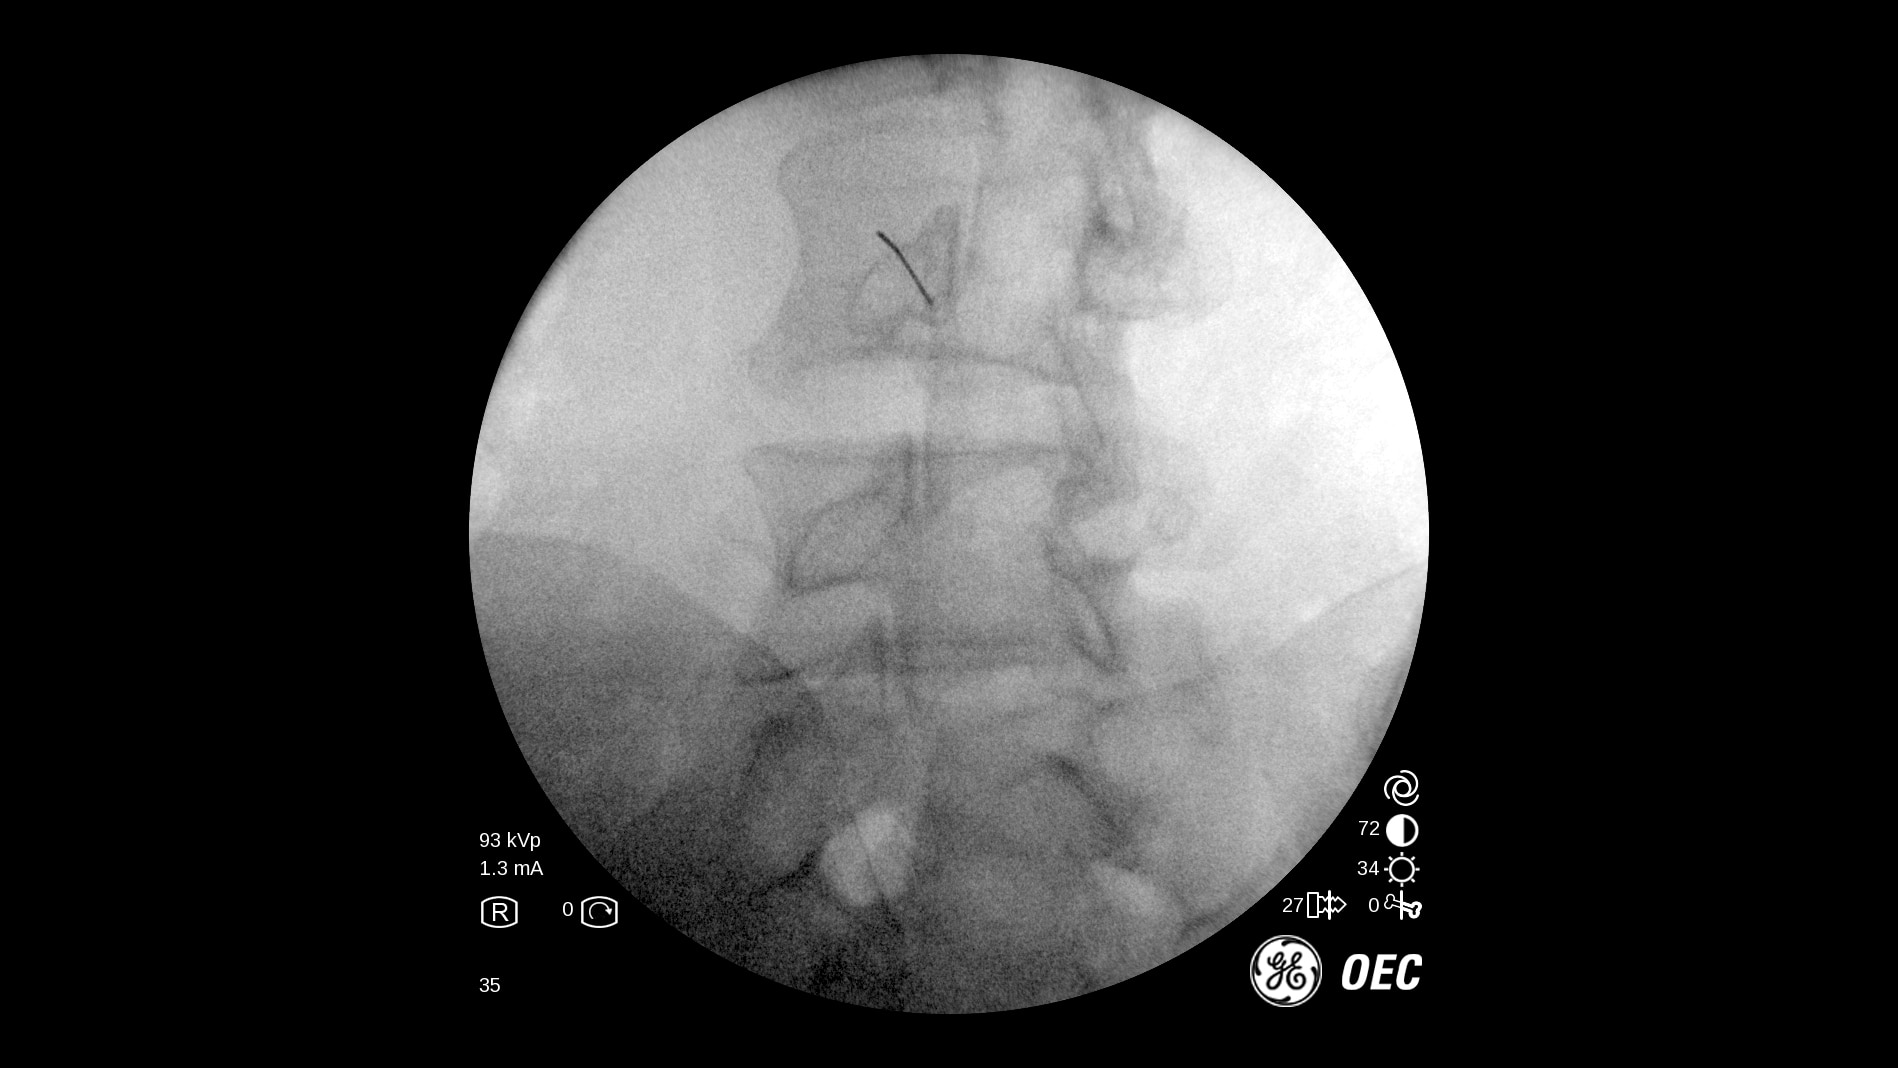

The OEC One all-in-one mobile C-arm offers superb imaging capabilities, made more accessible for a variety of procedures — from pain management to peripheral vascular. Enjoy image processing advancements in clear, detailed images.

Get the images you need without adjusting system settings from the first shot to the last shot with OEC image processing software.

OEC One utilizes automatic intelligence software to sense anatomy and provide high quality imaging at optimal mA and kV levels, even when anatomy is not properly centered in the field of view.